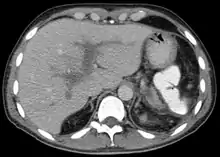

| Portal vein thrombosis seen with computed tomography. | |

The diagnosis of portal vein thrombosis is usually made with imaging confirming a clot in the portal vein; ultrasound is the least invasive method and the addition of Doppler technique shows a filling defect in blood flow. PVT may be classified as either occlusive or nonocclusive based on evidence of blood flow around the clot.[5] An alternative characterization based on site can be made: Type 1 is limited to the main portal vein, Type 2 involves only a portal vein branch (2a, or 2b if both branches are affected), and Type 3 if clot is found throughout both areas.[8] Determination of condition severity may be derived via computed tomography (CT) with contrast, magnetic resonance imaging (MRI), or MR angiography (MRA). Those with chronic PVT may undergo upper endoscopy (esophagogastroduodenoscopy, EGD) to evaluate the presence of concurrent dilated veins (varices) in the stomach or esophagus.[3] Other than perhaps slightly elevated transaminases, laboratory tests to evaluate liver function are typically normal.[1] D-dimer levels in the blood may be elevated as a result of fibrin breakdown.